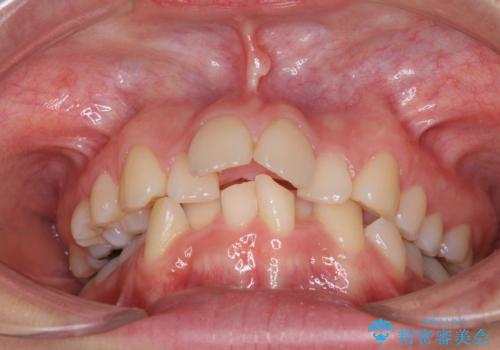

デコボコで飛び出した前歯 ワイヤー装置による抜歯矯正

- 上下前歯のデコボコと、飛び出した前歯を気にして来院された患者様です。

口元を積極的に引っ込めるために、上下左右の小臼歯計4本を抜歯することとしました。

咬み合わせが深く、咬合力強いため、補助装置を使用しながら積極的に口元を下げることとしました。